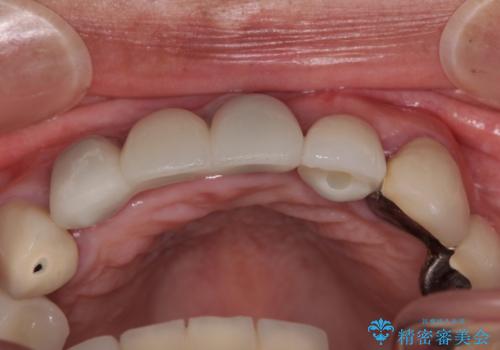

事前に仮歯の型取りをして用意をしていたため、インプラント埋入後に速やかに仮歯を装着しました。

インプラントの安定度も高く、抜歯と埋入から2か月後にはオールセラミッククラウンを装着することができました。